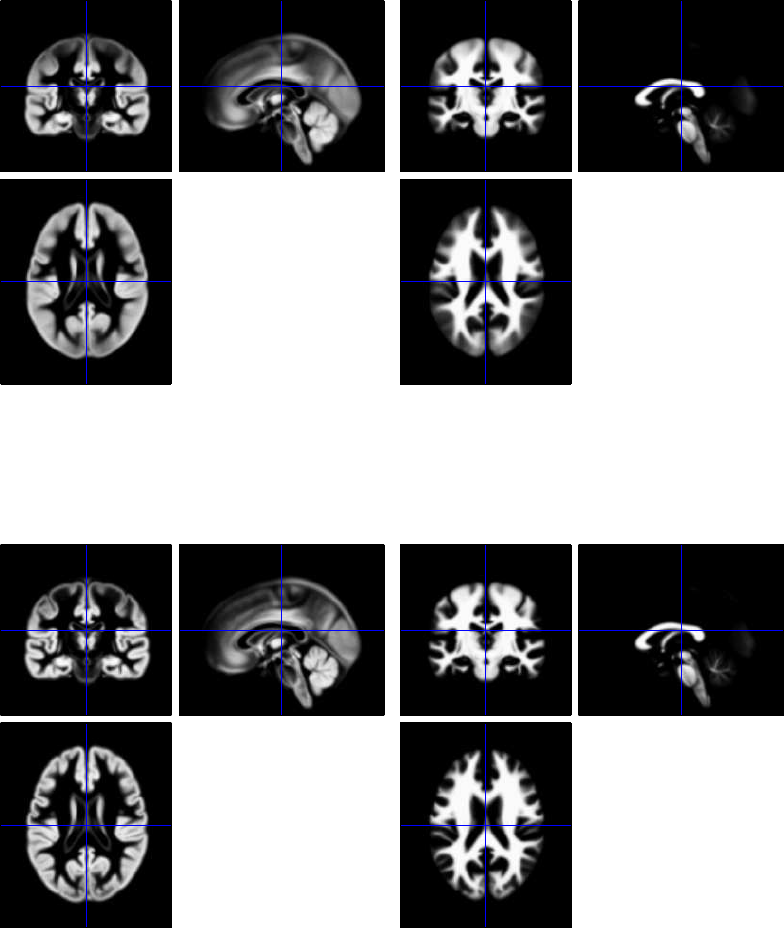

42.7.2 Normalisation/Segmentation of T1 images ...................422

42.7.3 Coregistration of mean EPI (fMRI) to T1 (sMRI) ..............422

42.7.4 Application of Normalisation parameters to EPI data ............422

42.7.5 Smoothing ....................................423

42.7.6 Creating a 1st-level (fMRI) GLM ........................423

42.7.7 Model Estimation ................................423

42.7.8 Setting up contrasts ...............................423

42.7.9 Group Statistics on fMRI data .........................425

42.8 Source Reconstruction ..................................425

42.8.1 Create Head Model ................................427

42.8.2 Model Inversion .................................428

42.8.3 Time-frequency contrasts ............................428

42.8.4 Group Statistics on Source Reconstructions ..................431

42.9 Group Source Reconstruction ..............................433

42.9.1 Group Statistics on Source Reconstructions ..................433

42.10Group MEEG Source Reconstruction with fMRI priors ................433

42.10.1 Group Statistics on Source Reconstructions ..................435